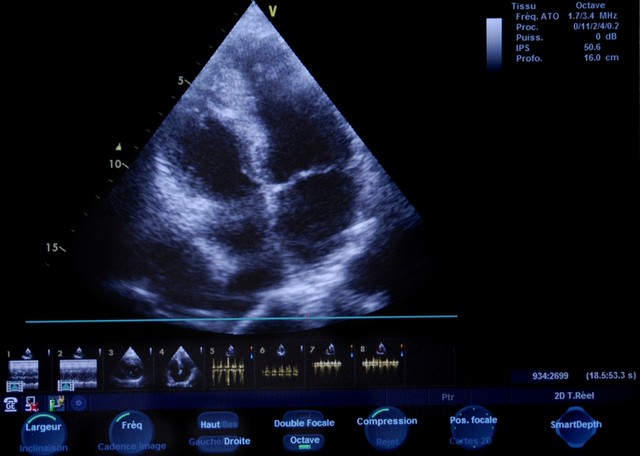

做心脏超声,能清楚看到心肌的厚度、心室的大小、心脏的收缩和舒张功能,还能排查有没有心室肥厚、瓣膜反流这些问题。早发现,就能早干预,避免小问题拖成心肌缺血、心衰的大麻烦。

我之前有个 40 岁的患者,低压常年 95 左右,总说胸口发闷,一开始没当回事,后来做心脏超声发现心肌已经轻度肥厚了。赶紧调整生活方式,配合中药调理,半年后低压降到 85,复查心脏超声,心肌厚度也恢复了正常。